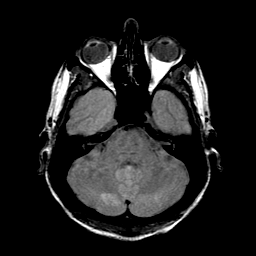

Sarcoma, MR Study #1 mr-pd -- Slice #5

[Home][Help][Clinical] Slice 5